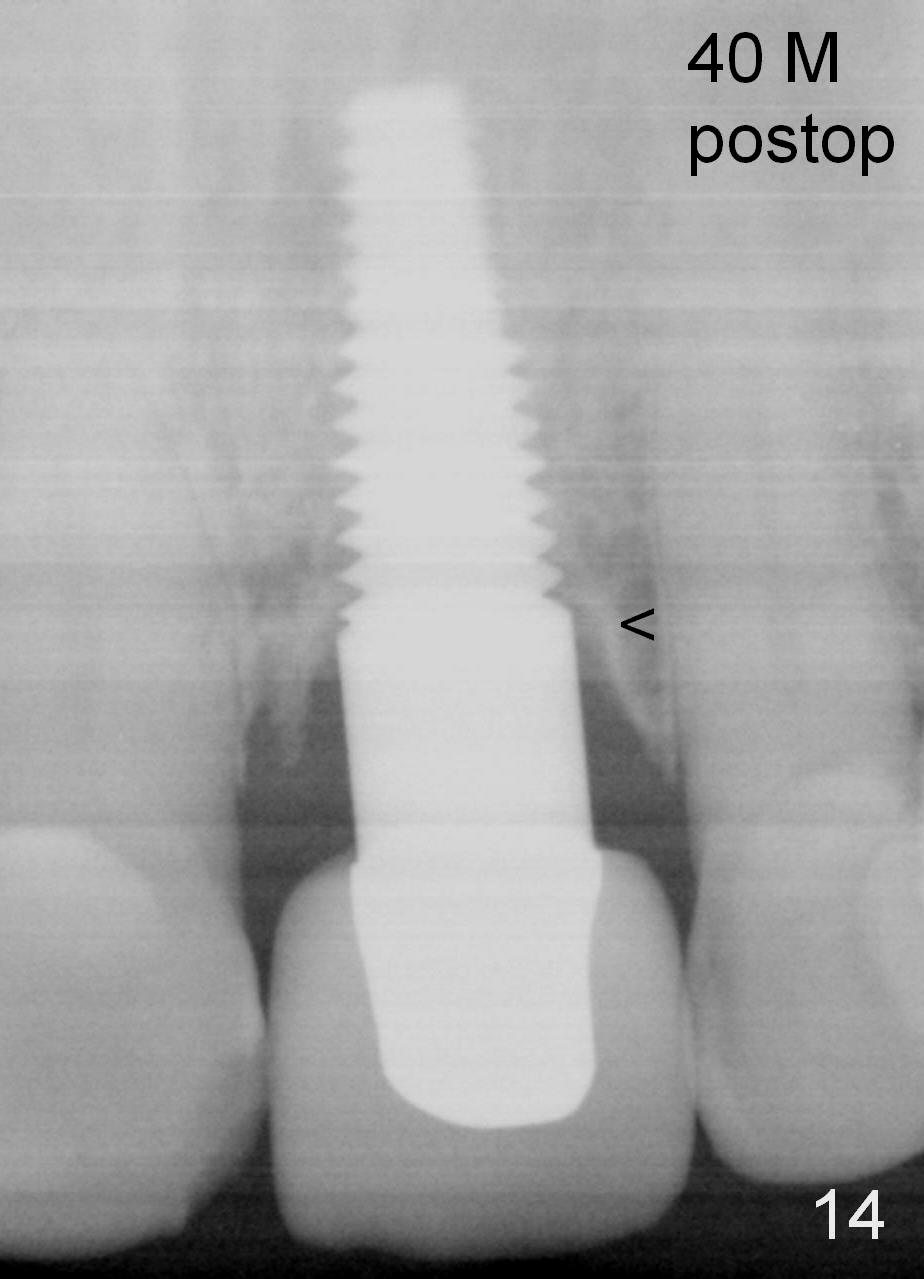

Fig.14: 40 months postop (21 months post cementation). The cortical bone forms (<).